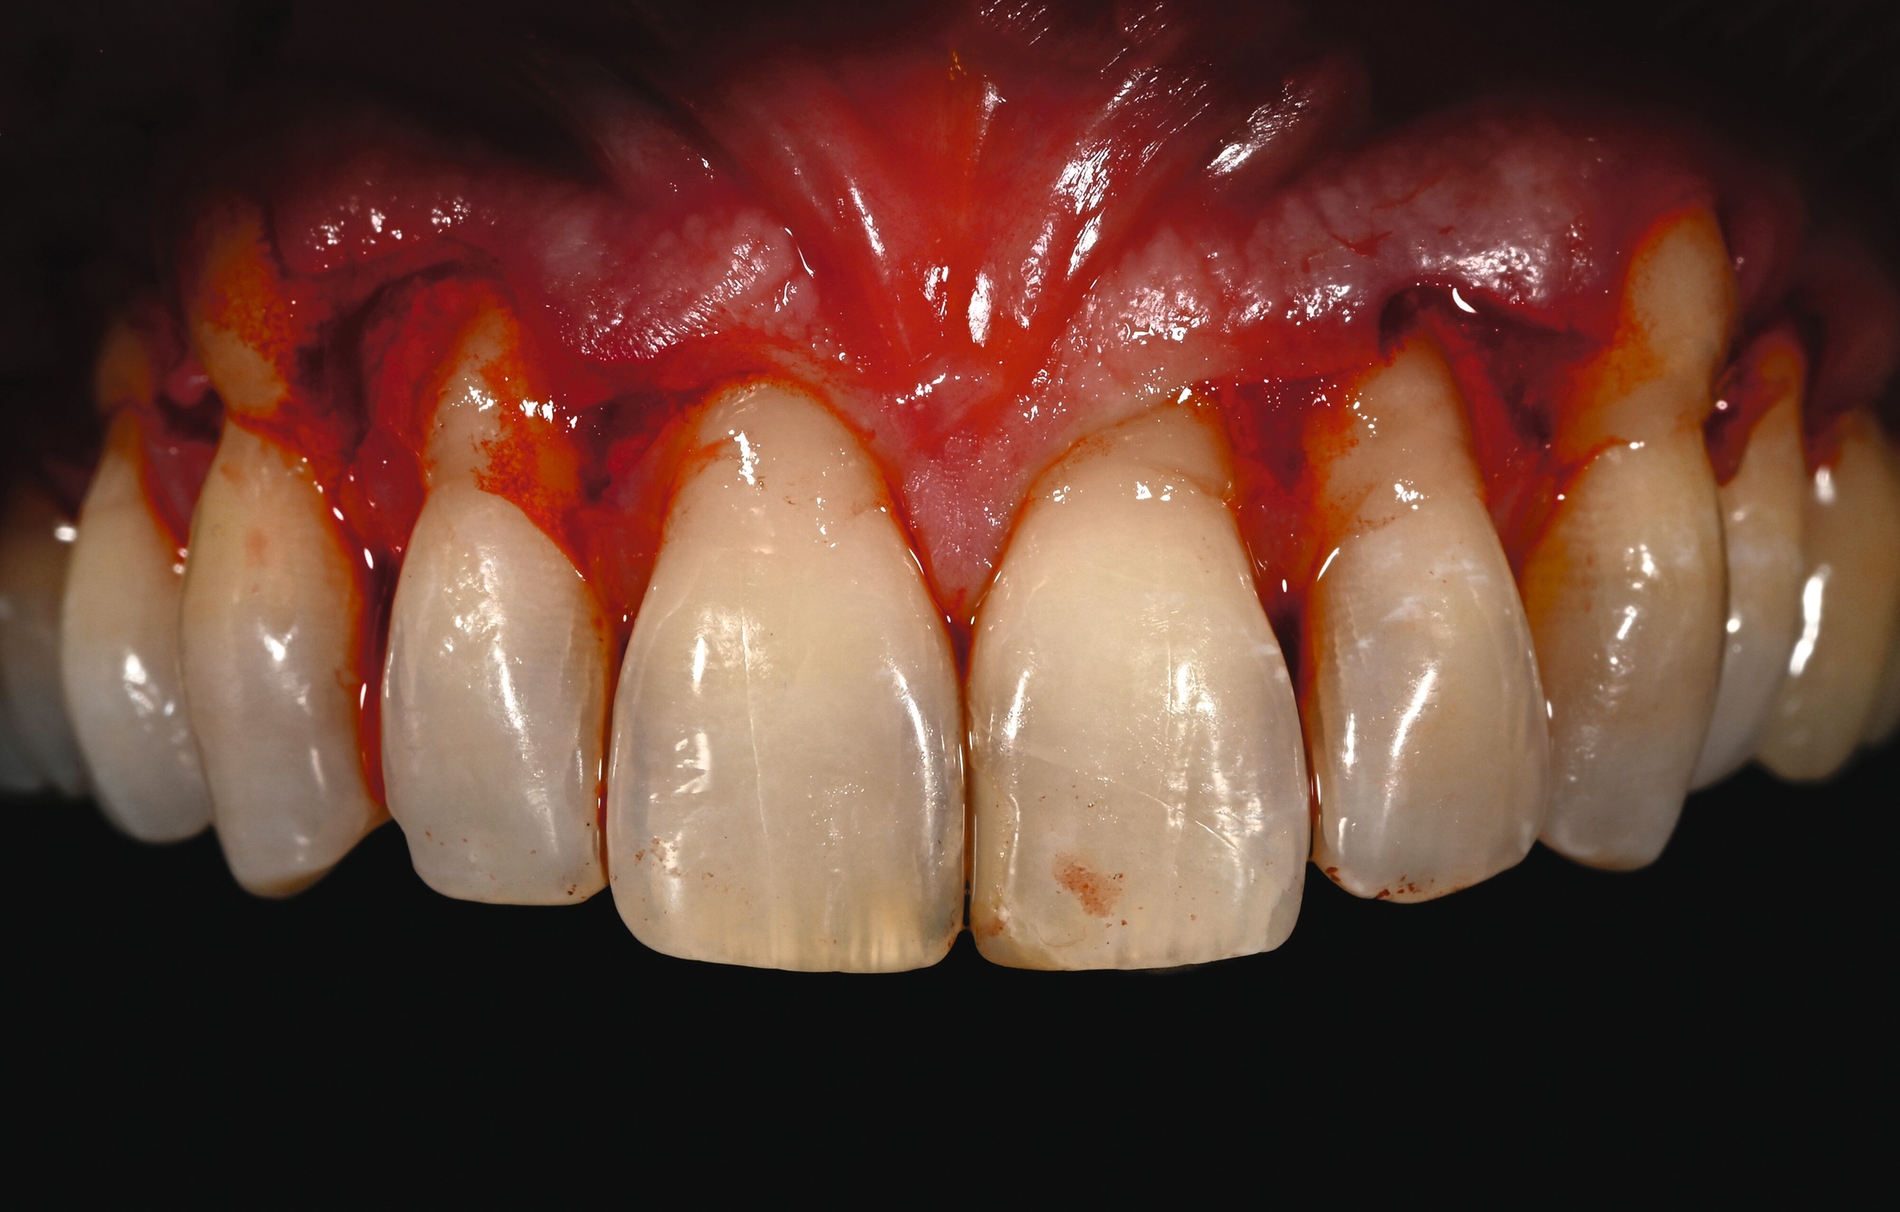

Trotz des Verbleibs des Epithels kann es zu sekundärer Wundheilung mit entsprechender Morbidität postoperativ kommen, besonders bei Techniken, die mehrere Inzisionen beinhalten, wie den sogenannten Trap-Door-Techniken, so dass sich die „Single-Incision-Technik“ durchgesetzt hat [Fickl et al., 2014]. Gegen eine übermäßige Blutung und postoperative Morbidität empfiehlt sich klinisch die routinemäßige Anwendung einer Verbandplatte, entweder in der Tiefziehtechnik oder präoperativ mittels eines Thermoplasts, so dass sich früh ein stabiles Blutkoagel bildet und die Wundheilung an der Entnahmestelle ungestört ablaufen kann. Dadurch wird die Morbidität klinisch deutlich reduziert. Das sBGT zeigt ästhetisch sehr gute Ergebnisse mit Blick auf Oberflächenstruktur sowie Farbe und kann unter anderem im Rahmen der Envelope- oder Tunneltechnik oder auch über einer Extraktionsalveole bewusst exponiert belassen werden, um zusätzlich befestigte Gingiva zu gewinnen.

Die Wundheilung nach dieser Technik erfolgt anders als beim sBGT immer sekundär, somit wurden bei Vergleichsstudien eine signifikant erhöhte Morbidität, Schwellungen und ein erhöhtes Nachblutungsrisiko beschrieben [Del Pizzo et al., 2002; Griffin et al., 2006], was jedoch bei entsprechender Versorgung des Gaumens umgegangen werden kann [Zucchelli et al., 2010]. Die Versorgung der Spenderregion kann mit Kollagenvlies, Cyanoacrylatkleber, Verbandplatte oder einer Kombination erfolgen. Dies kann die Morbidität deutlich reduzieren [Tavelli et al., 2019b]. Ein Vorteil von dBGT ist die Stabilität der Gewebedicke im Laufe der Zeit, was im Gegensatz zur beschriebenen Schrumpfung von sBGT steht, die häufig beobachtet wird [Zucchelli et al., 2018].

Eine Übersichtsarbeit, die sBGT und dBGT im Rahmen der Rezessionsdeckung verglich, empfahl primär die Anwendung des dBGT. So lag die mittlere Wurzelabdeckung nach zwölf Monaten mit dem sBGT bei 89,3 Prozent im Vergleich zu 94 Prozent beim dBGT. Die Daten der dBGT-Gruppe stützten sich jedoch nur auf die Ergebnisse einer einzigen Arbeitsgruppe und die Gruppen mit der höchsten durchschnittlichen Wurzeldeckung wurden für das sBGT berichtet, so dass hier ein gewisser Centereffekt vermutet werden kann. Weiterhin besteht bei dBGT ein gewisses Risiko für ästhetische Komplikationen wie eine keloidartige Narbenbildung, eine unnatürliche Randsituation oder eine deutlich hellere und glattere Oberfläche, wenn das Transplantat nicht korrekt gehandhabt wird, der Decklappen sehr dünn ist oder das Transplantat offen einheilt [Gluckman et al., 2019; Zucchelli et al., 2014b].

Neuere Daten haben weiterhin gezeigt, dass die Durchblutung des Decklappens durch ein dBGT signifikant länger reduziert ist als bei einem sBGT, was in der Folge zu häufiger auftretenden späten Komplikationen wie Zystenbildungen führt [Ragghianti-Zangrando et al., 2021]. Die vollständige Entfernung des Epithels – egal ob intra- oder extraoral – wird nicht immer erreicht [Couso-Queiruga et al., 2023], was letztlich zu Problemen bei der Einheilung mit unvollständiger Verbindung zum Decklappen oder mit der Wundunterlage wie der Wurzeloberfläche führen kann. So wurde von einer deutlich erhöhten Dehiszenzrate in etwa jedem zweiten Fall bei dicken dBGT (> 1,5 mm) mit entsprechend reduziertem ästhetischem Ergebnis berichtet [Zucchelli et al., 2014a].